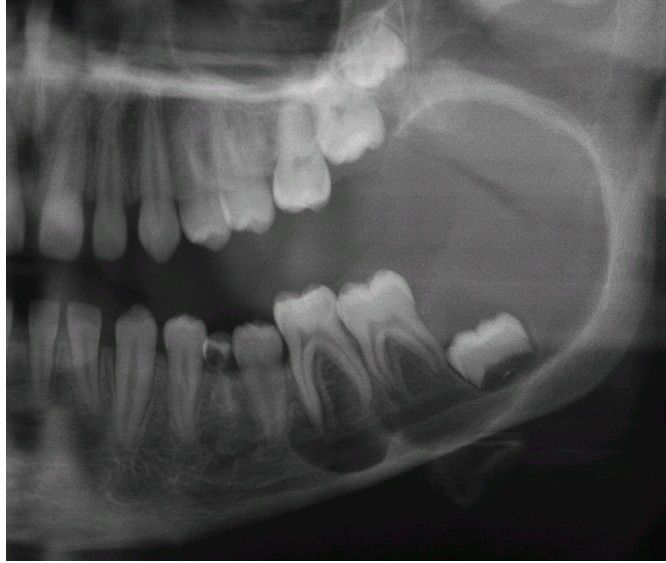

Unicystic Ameloblastoma.

A large radiolucency associated with the crown of the developing mandibular third molar.

Oralpathology

Radiograph

Ameloblastoma